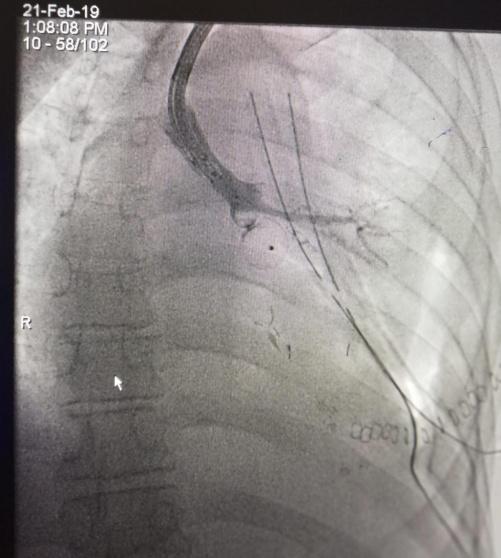

وكان المريض قد عانى من وجود فتحة في قصبته الهوائية باتجاه الرئة نتيجة التهابات سابقة، ما سبب له آلاماً شديدة وتسريباً للهواء، فيما أجريت العملية عن طريق المنظار دون الحاجة لفتح صدر المريض وإغلاق الفتحة بشكل كامل، وذلك من خلال إدخال دعامة تستعمل عادة لإغلاق فتحات القلب.

من جهته، قال الدكتور محمد أبو طاقة إن العملية أنقذت حياة المريض الذي كان يعيش حياة صعبةً خلال آخر أسبوعين، مشيراً إلى أن التحدي الأكبر في إجراء مثل هذه العملية كان يتمثل في قدرتهم على إغلاق الفتحة الموجودة في هذه القصبة دون إغلاق بقية القصبات الهوائية، بالإضافة إلى حساسية منطقة العملية كونها ستجرى في الفراغ الموجود بين القصبة والقلب، بحيث نتجنب إحداث أي ضرر بعضلة القلب خلال إغلاق الفتحة.